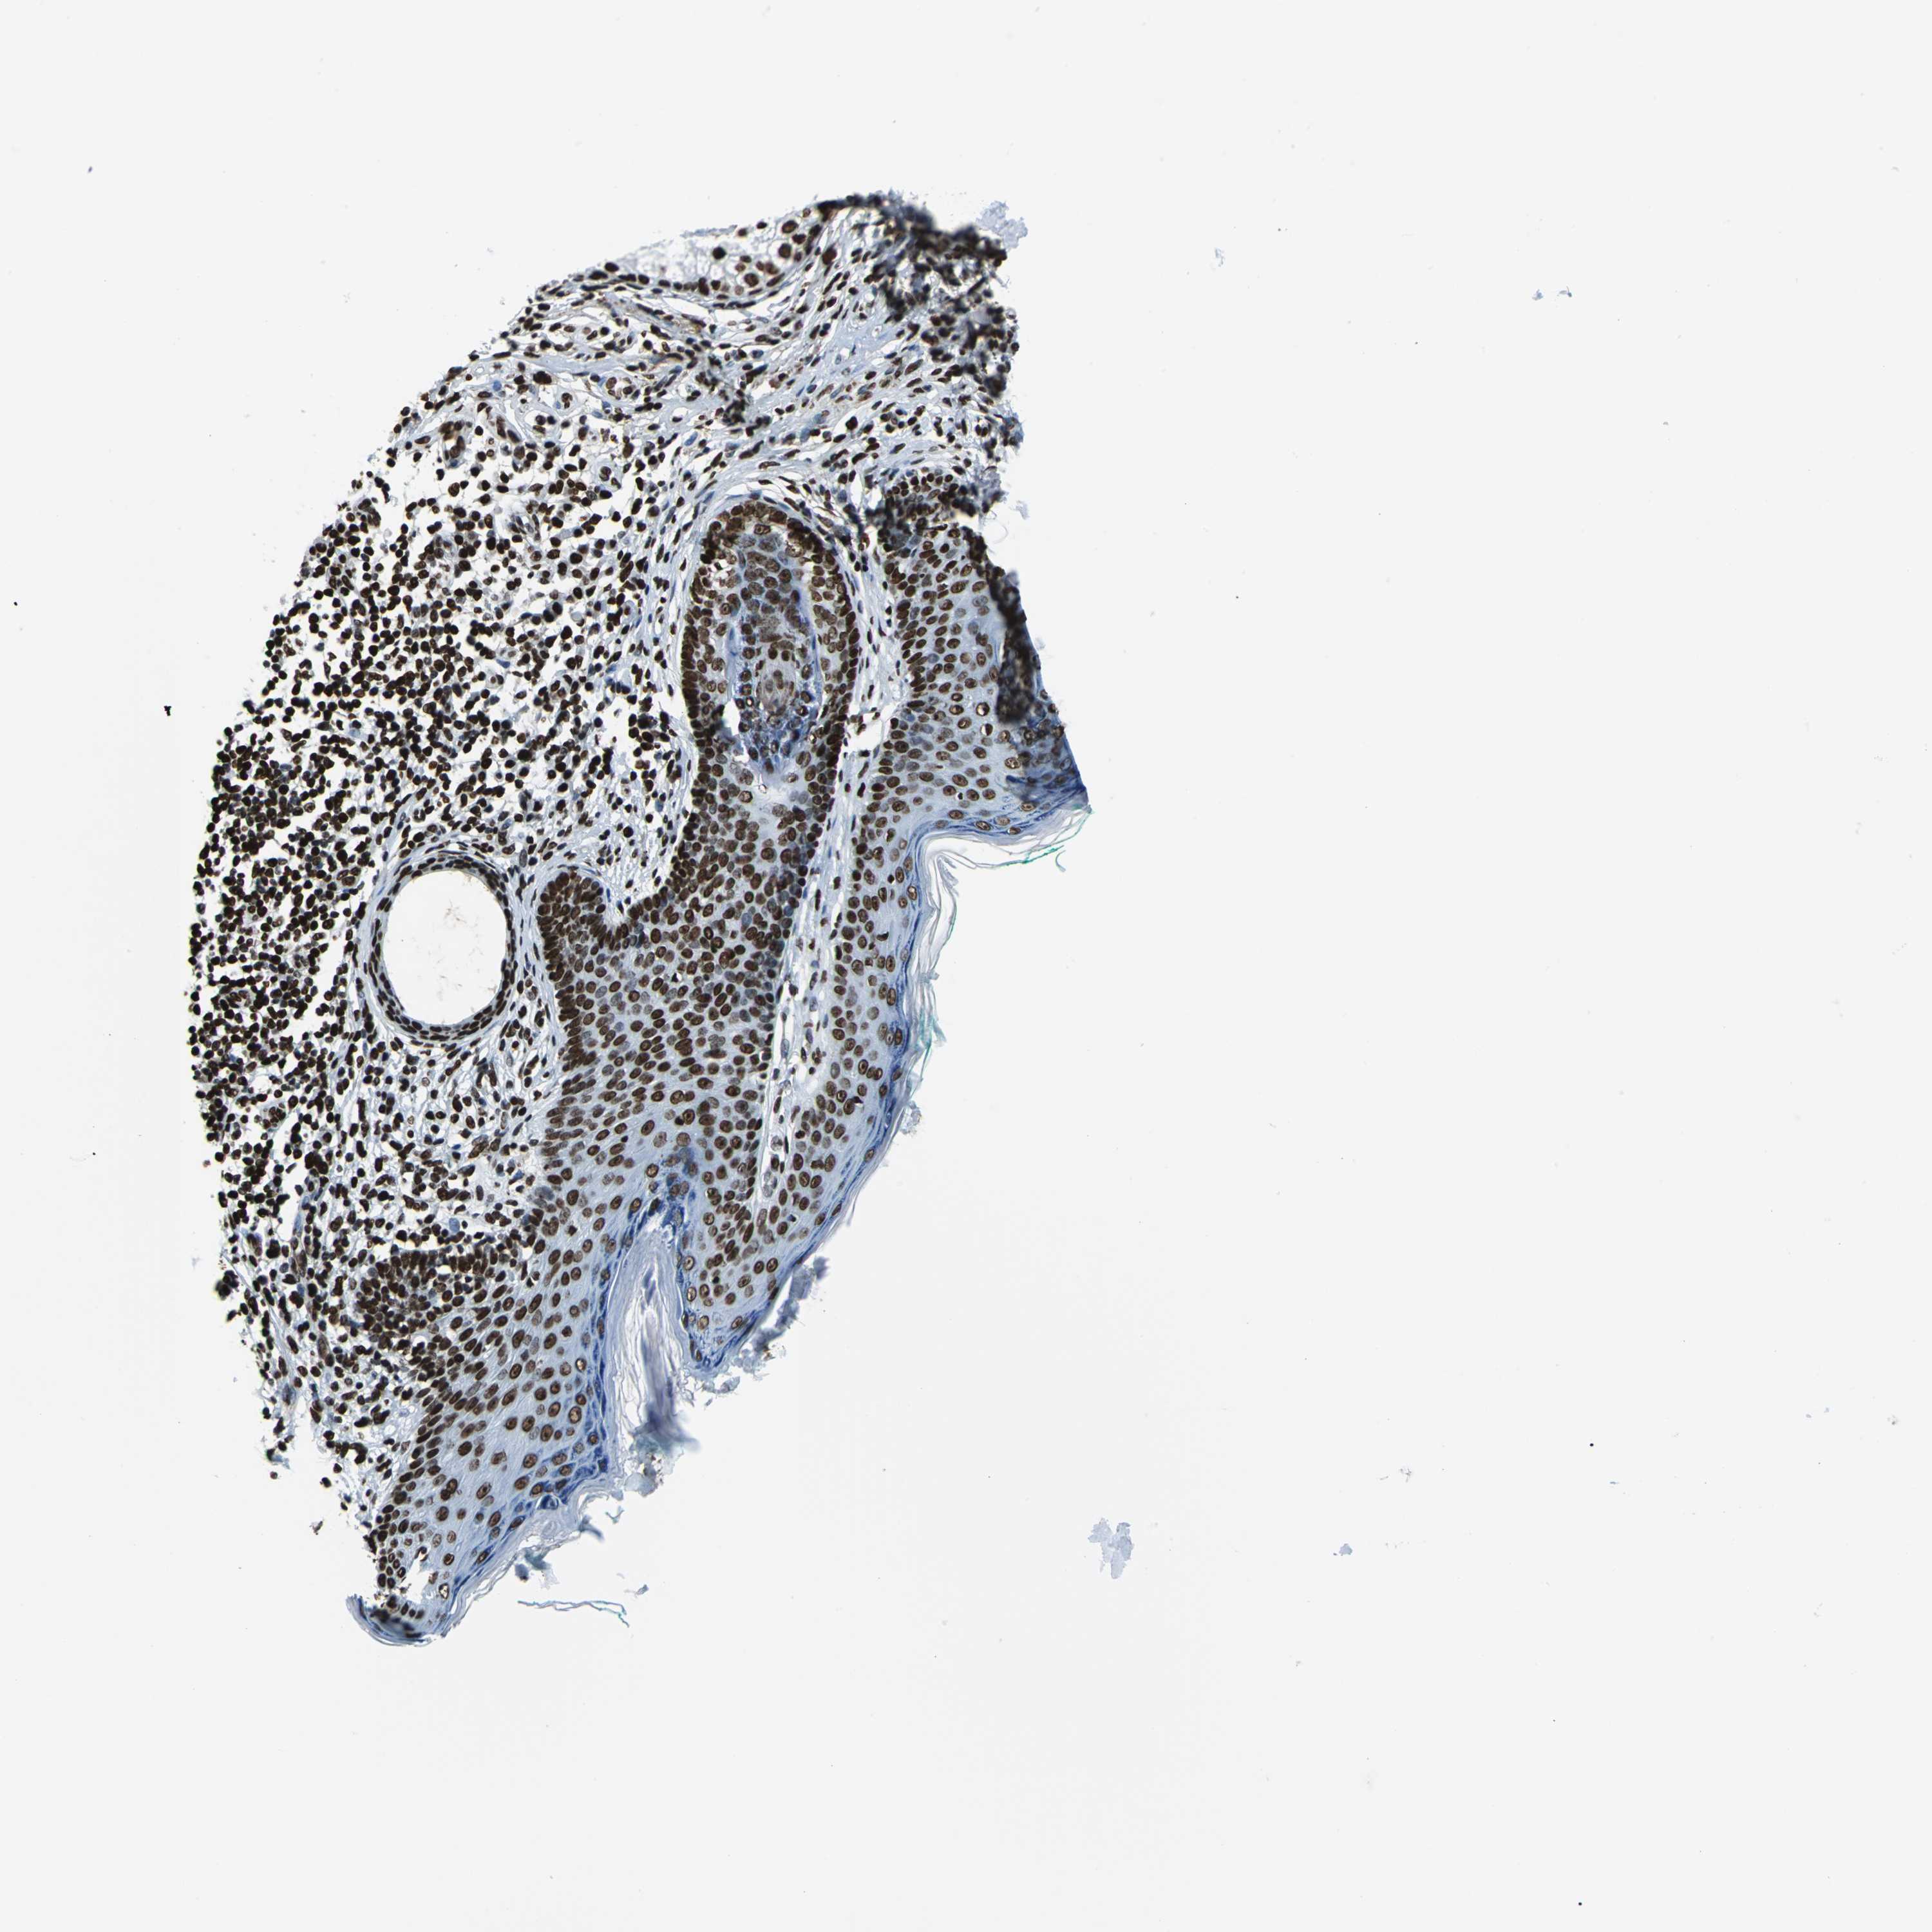

SKIN CANCER - Protein expressioni

A mouse-over function shows sample information and annotation data. Click on an image to view it in a full screen mode. Samples can be filtered based on level of antibody staining by selecting one or several of the following categories: high, medium, low and not detected. The assay and annotation is described here.

Each image is clickable and will lead to virtual microscopy that enables deeper exploration of all samples and also displays staining intensity scores, fraction scores and subcellular localization as well as patient and tissue information for each sample.

Antibody CAB004294

Staining

High

Medium

Low

Not detected

Intensity

Strong

Moderate

Weak

Negative

Quantity

>75%

75%-25%

<25%

None

Location

Nuclear

Cytoplasmic/membranous

Cytoplasmic/membranous,nuclear

Basal cell carcinoma

Squamous cell carcinoma, NOS